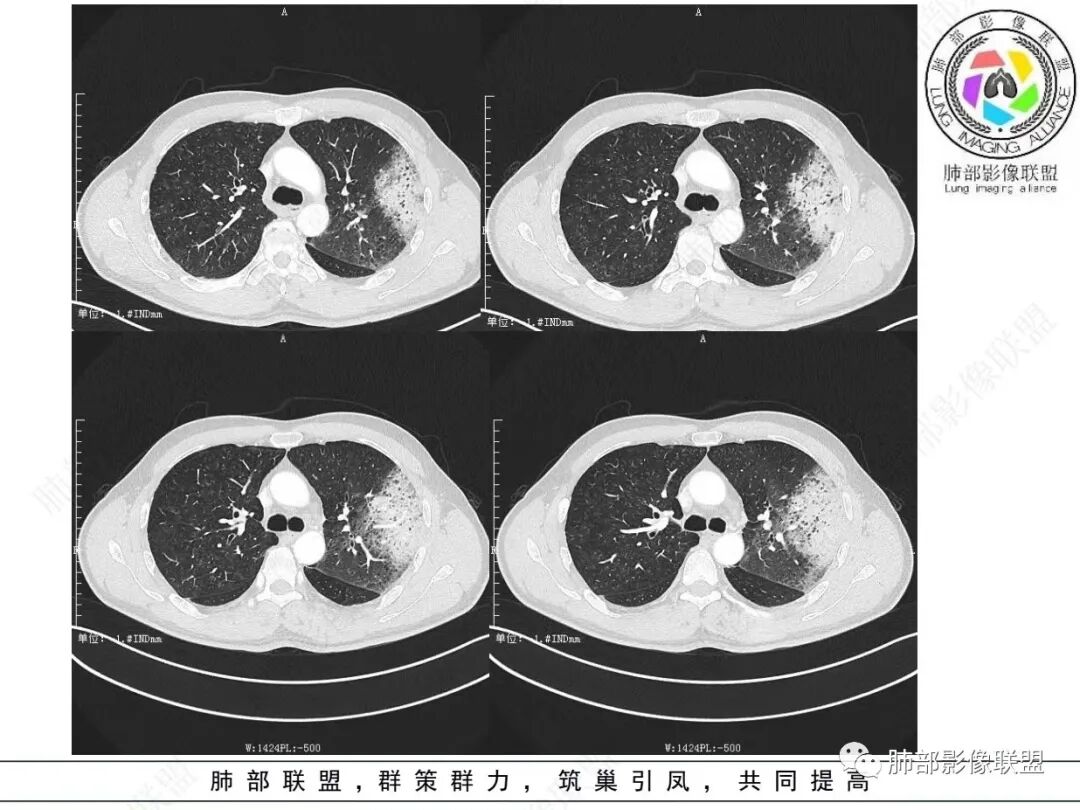

病史提供影像表现就不赘述,考虑肺粘液腺癌,两肺弥漫性结节,肺内播散?

左肺上叶斑片实变影,内有周边磨玻璃影并小叶内间质增厚,增强实变影内有肺动脉走形,考虑肺炎型肺癌;双肺弥漫分布小结节,细支气管炎?过敏性肺炎?转移?

左肺上叶片状实变,内可见多发空泡及蜂窝影,斜裂上方可见相同病灶由于斜裂阻挡呈重力分布,强化可见血管造影征,双肺弥漫分布气腔结节,临床咳白色粘液痰,考虑粘液腺癌

男,46,咳嗽半年,加重10天,白粘痰,偶有痰血。胸部CT:左肺上叶舌叶大片实变影,边缘GGO,长轴沿胸膜及叶裂展开,重力依赖,胸膜叶裂阻隔,内见蜂窝,钱币征,枯枝。强化不均匀,血管造影征。考虑粘液腺癌,鉴别大叶性肺炎、干酪性肺炎等。

2.左肺上叶大片状混合密度影,未见空洞,实变影主要位于胸膜下,长轴与胸膜平行,实变区内部密度不均、其内可见多发小斑片状低密度影,磨玻璃影多位居肺门一侧,可见网格,磨玻璃影边界多可分辨,重力分布趋势。病灶区支气管显示较为通畅,进入外围实变区渐至消隐。病灶轻度不均匀低强化,病灶区肺动脉显示较良好,未见破坏。

双肺广泛分布微小磨玻璃密度结节影,腺泡结节样分布,密度大小较为均匀一致。